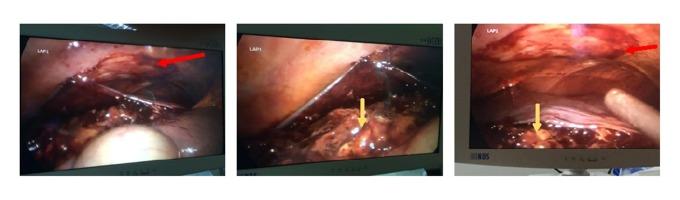

BACKGROUND Gastrointestinal stromal tumors (GISTs) are rare gastrointestinal neoplasms. The spontaneous rupture of a jejunal GIST is very rare and spontaneous rupture of liver metastasis from an intestinal GIST is even rarer with only a few cases reported in the literature. CASE REPORT In this article, we reported a case of spontaneous rupture of a liver metastasis from a malignant jejunal GIST that presented with active tumoral bleeding, hypovolemic shock, and hemoperitoneum. The patient was successfully treated with arterial embolization of the tumor. CONCLUSIONS In appropriately selected patients, arterial embolization appears to be an effective safe treatment for a GIST metastasis rupture.